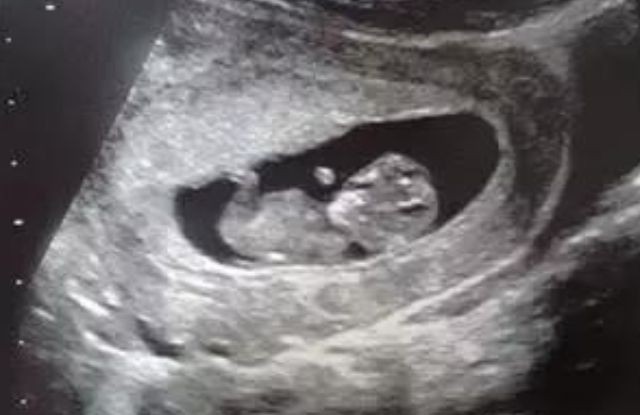

10. Hafta Anne Karnı Bebek Ultrason Görüntüleri